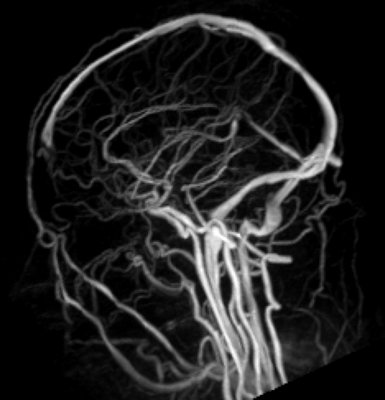

Целью селективной церебральной ангиографии при SP является исключение другой сосудистой патологии, характеризующейся артериовенозным шунтированием, а при обнаружении SP - подробное изучение его ангиоархитектоники, идентификация всех венозных коллекторов, соединяющих синус и экстракраниальное образование [1, 25]. В редких случаях проводится венография путем прямой пункции образования [46, 49]. Проведенная селективная церебральная ангиография больному М. позволила верифицировать SP.

УЗИ - При допплере может показать связь с поверхностными венами и дуральными венозными синусами.

МРТ- Характеристики сигнала могут варьироваться из-за медленного тока крови. МР-ангиография позволяет определить венозную природу поражения.